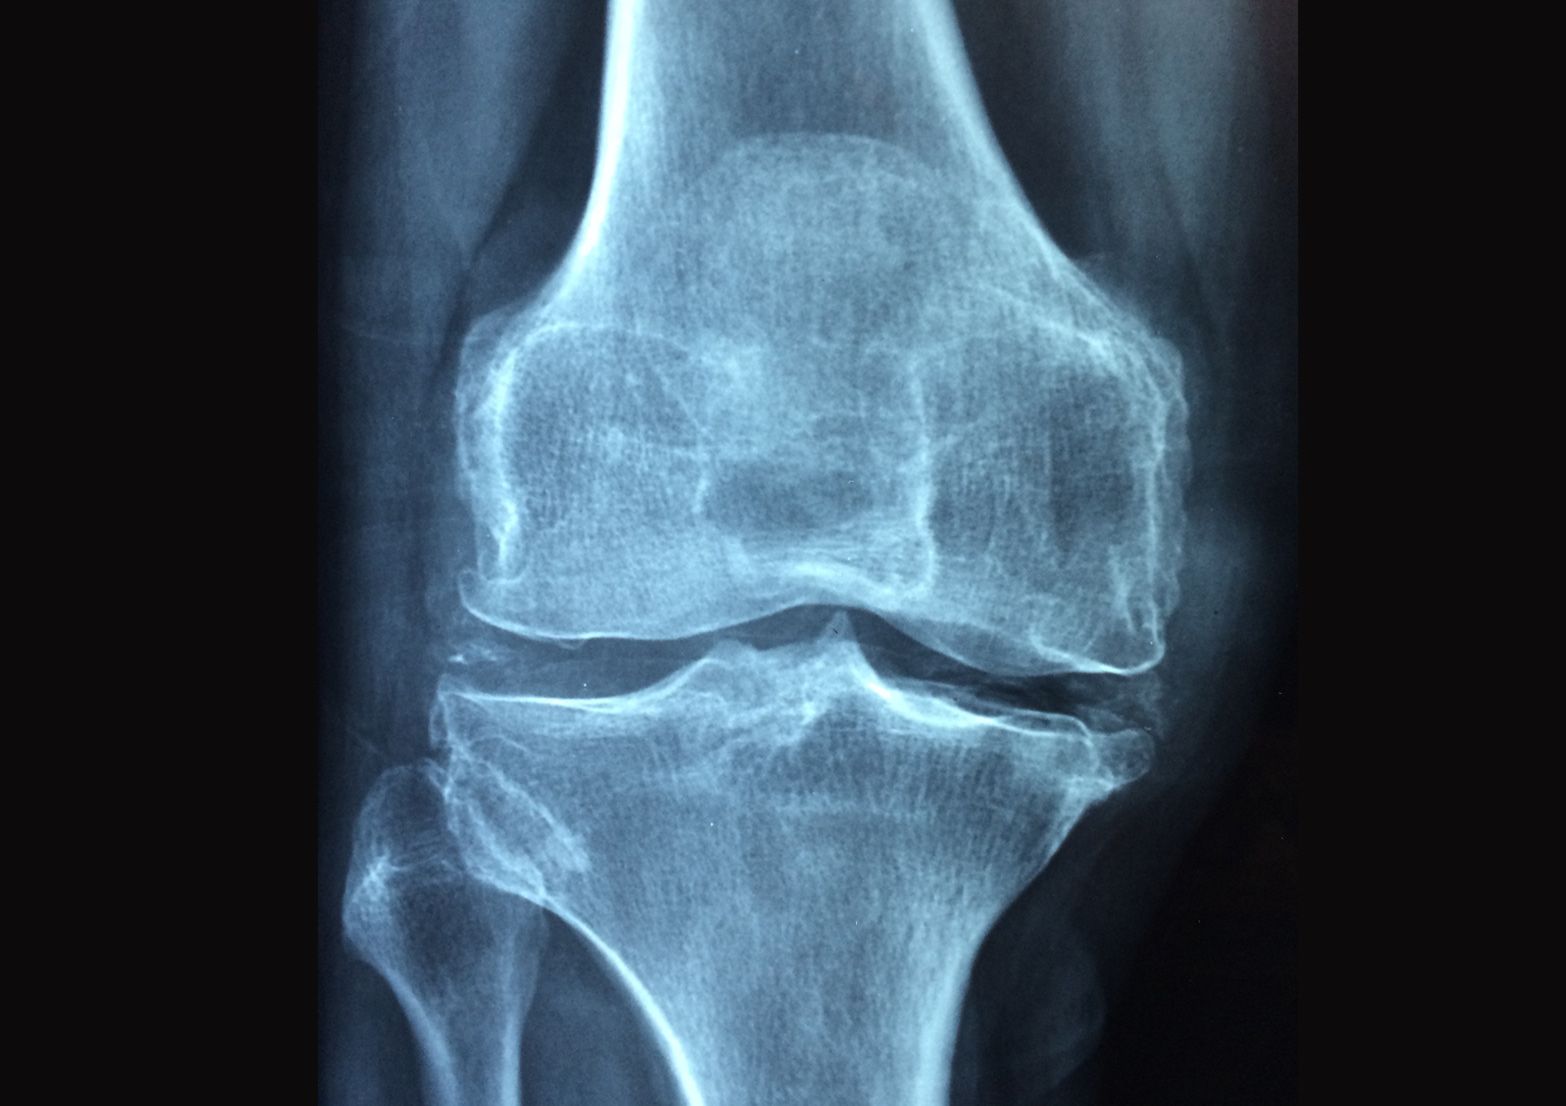

Laserterapia ad alta potenza: terapia indicata per eliminare il dolore e combattere le infiammazioni in tendiniti, fasciti, artrosi, capsuliti, meniscopatie, ecc..

Magnetoterapia: indicata per consolidazione di fratture, osteoporosi, dolori articolari, disturbi reumatici, lesioni delle cartilagini articolari, fibromi algia, ecc..